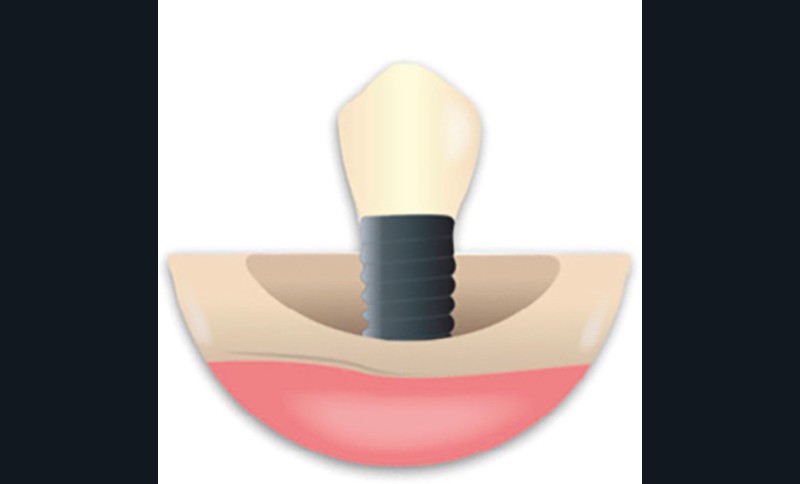

En ce qui concerne le traitement de la péri-implantite, l’identification et le contrôle des facteurs de risque locaux et systémiques, ainsi que la qualité des tissus mous environnants, sont des facteurs à prendre en compte. En ce qui concerne la partie prothétique, une évaluation minutieuse de la prothèse doit être faite pour envisager si nécessaire une nouvelle conception. L’approche électrolytique exige que la prothèse sur l’implant…